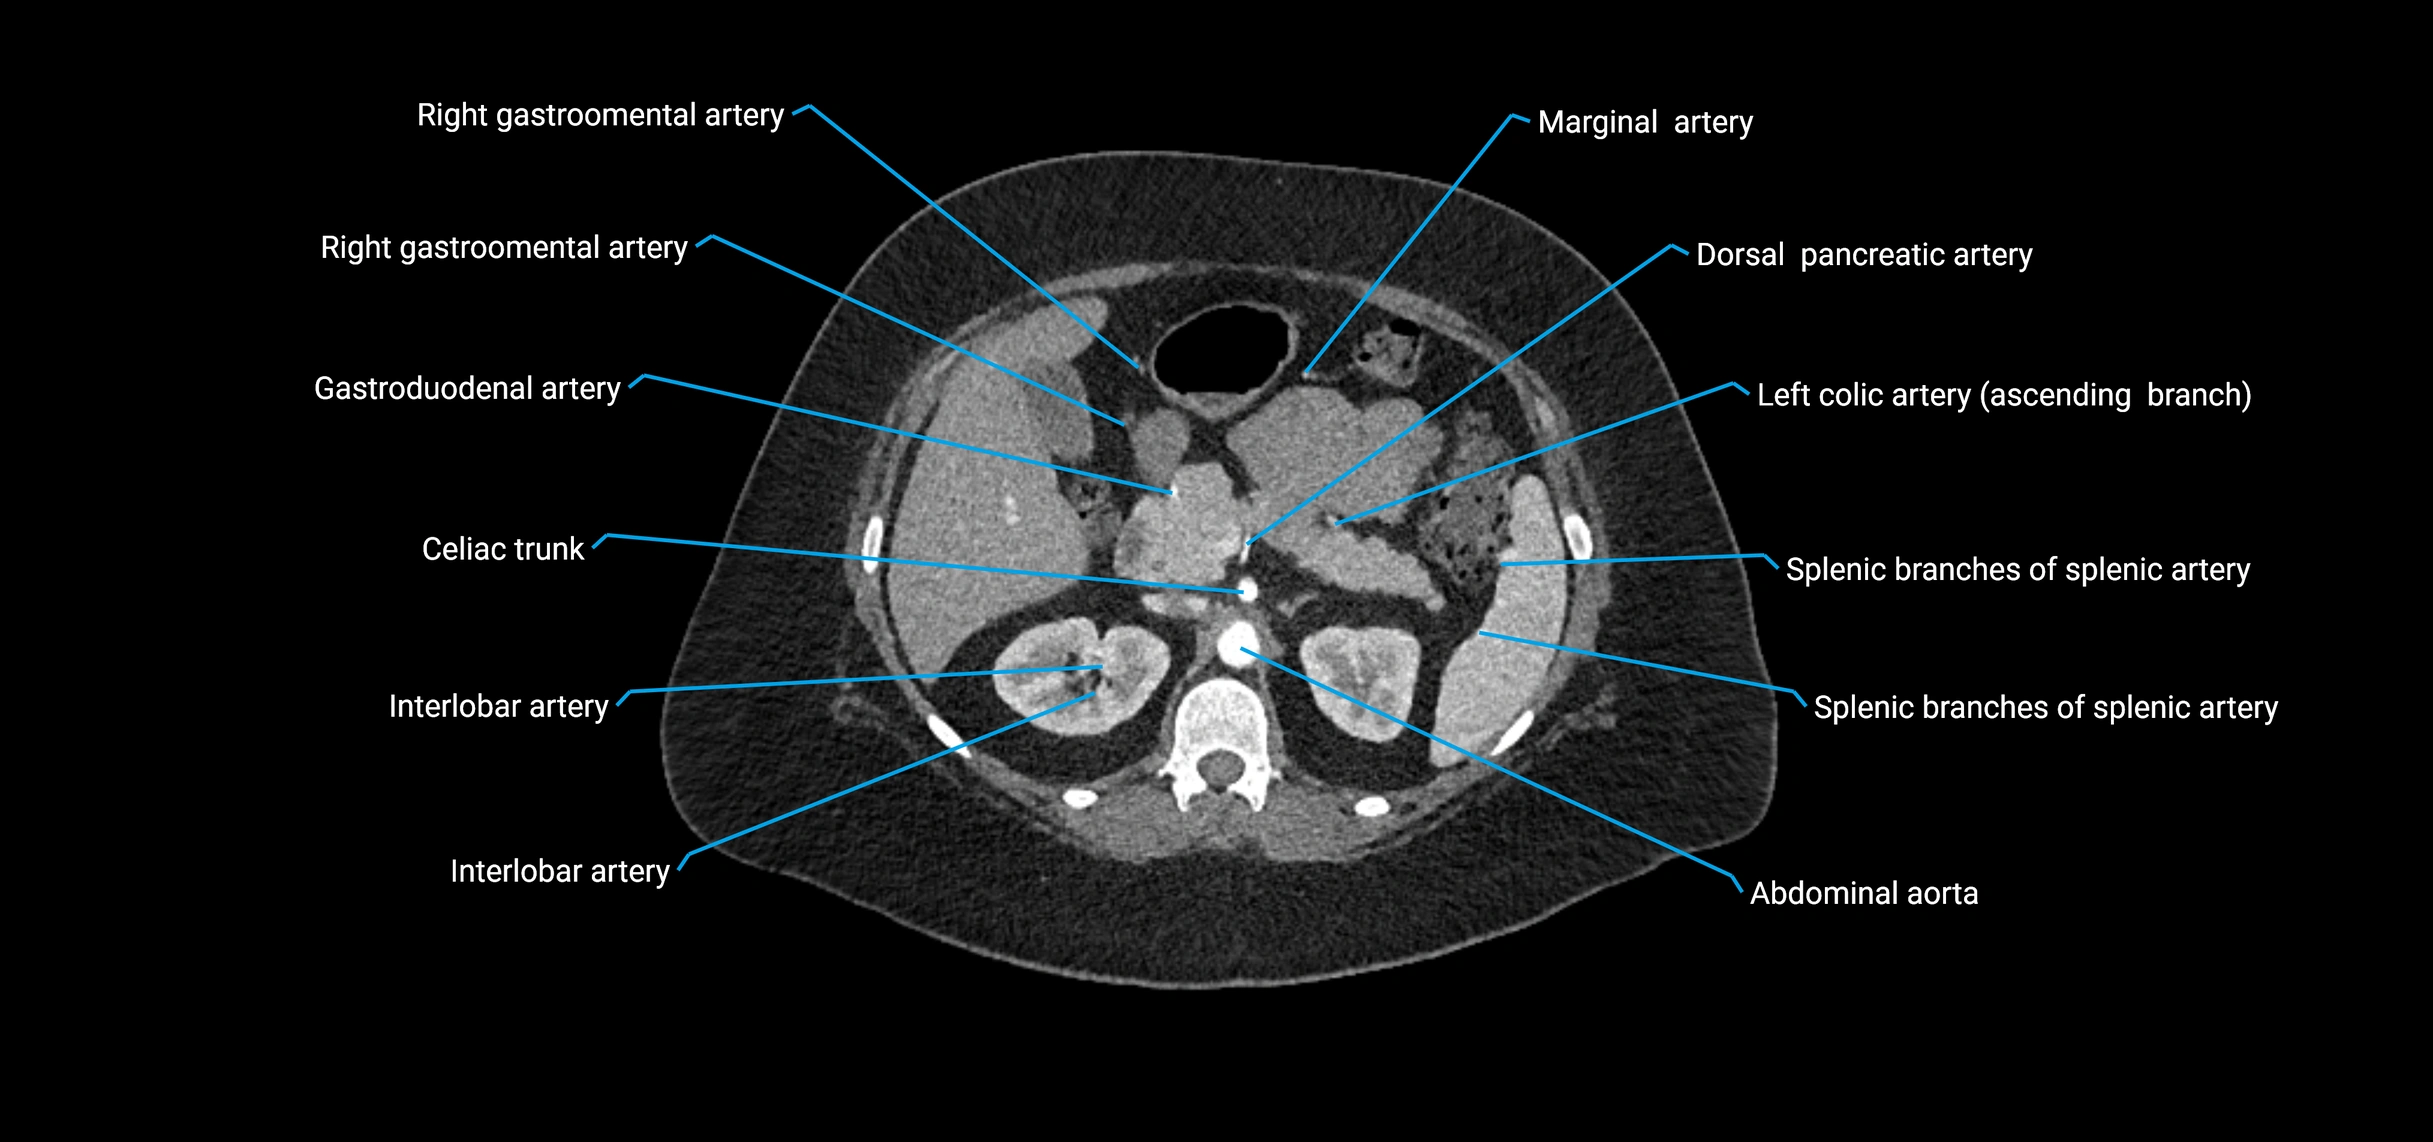

Contrast-enhanced CT (CTA):

• Gold standard for abdominal aortic imaging

• Provides excellent detail of lumen, wall, aneurysm, thrombus, and branch vessels

• Multiplanar and 3D reconstructions help in aneurysm measurement, stent graft planning, and dissection evaluation

• Detects acute rupture, traumatic injury, or occlusion with high sensitivity